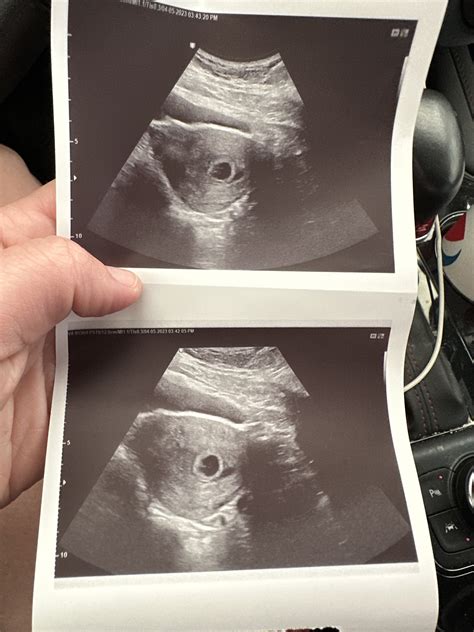

A 6 week sonogram twins is typically the first ultrasound performed during a twin pregnancy. At this stage, the embryos are still very small, but the ultrasound can detect the presence of two gestational sacs, which are the early structures that will develop into the amniotic sacs. This confirmation is essential for early detection and monitoring of twin pregnancies.

• Detection of Gestational Sacs: The primary goal of the 6 week sonogram twins is to detect the presence of two gestational sacs. Each sac contains an embryo and will eventually develop into an amniotic sac.

• Heartbeat Detection: While it is possible to detect fetal heartbeats at 6 weeks, it is not always guaranteed. The heartbeats may be visible as flickering movements within the gestational sacs.

• Presence of Gestational Sacs: The detection of two gestational sacs confirms a twin pregnancy. This is a crucial finding that sets the stage for ongoing monitoring and care.